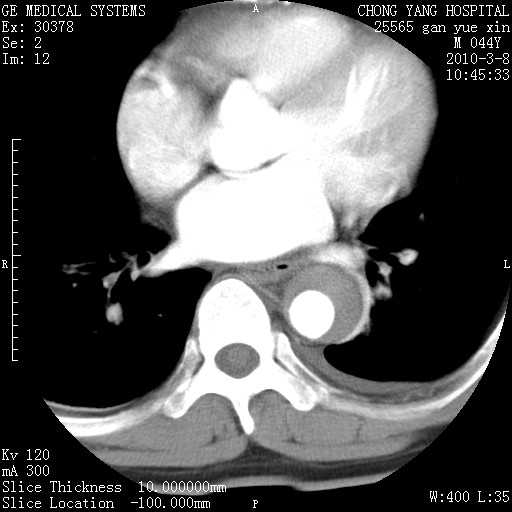

标题: CT24940:主动脉增强,典型病例。 [打印本页]

标题: CT24940:主动脉增强,典型病例。

夹层动脉瘤。

动脉夹层

夹层动脉瘤,典型

主动脉夹层。

动脉夹层的分型:

⒈debakey分型:根据主动脉夹层累及部位,分为三型:ⅰ型:原发破口位于升主动脉或主动脉弓部,夹层累及升主动脉、主动脉弓部、胸主动脉、腹主动脉大部或全部,少数可累及髂动脉。ⅱ型:原发破口位于升主动脉,夹层累及升主动脉,少数可累及部分主动脉弓。ⅲ型:原发破口位于左锁骨下动脉开口远端,根据夹层累及范围又分为ⅲa,ⅲb。ⅲa型:夹层累及胸主动脉。ⅲb型:夹层累及升主动脉、腹主动脉大部或全部。少数可累及髂动脉。

⒉stanford分型:a型:夹层累及升主动脉,无论远端范围如何。b型:夹层累及左锁骨下动脉开口以远的降主动脉。

夹层动脉瘤,少量胸水

夹层动脉瘤;左侧少量胸腔积液。

典型主动脉夹层。